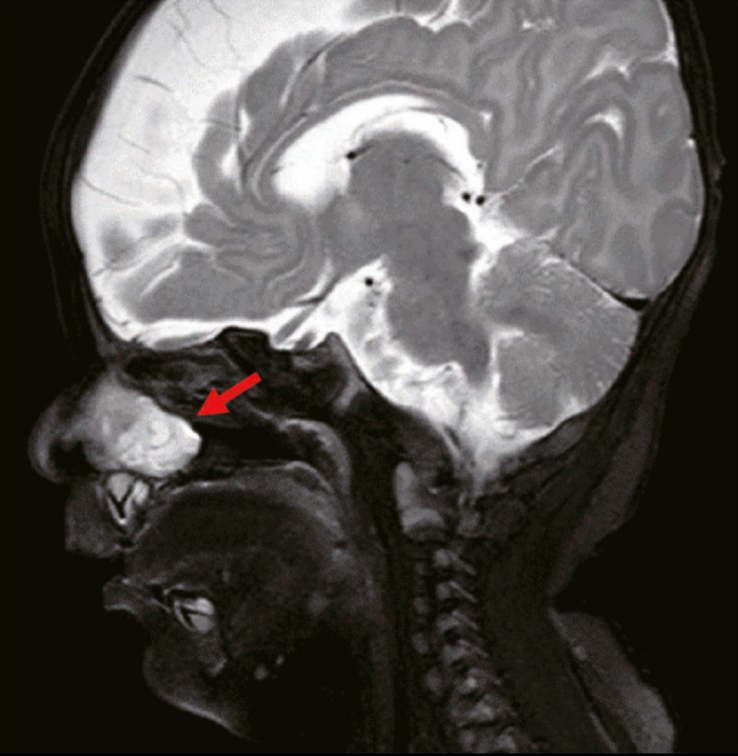

一名2个月大的男孩因出生后出现的鼻塞而接受治疗。右侧鼻腔阻塞明显,持续存在,并逐渐加重,导致奶瓶喂养时窒息。纤维支气管镜检查显示右鼻腔靠近咽部有2.0cm×1.5cm的息肉样物质(图1)。鼻咽计算机断层扫描(CT)显示右鼻腔软组织中有小面积高密度影。

肿块的放射密度约为26-35个Hounsfield单位,未见明显增强;此外,颅底无明显骨缺损,肿瘤与大脑不相通。磁共振成像(MRI)显示右侧鼻腔和前庭软组织有高密度影(图2)。软组织肿块大小约为22.1mm×17.3mm×10.9mm,呈不均匀强化。此外,肿块延伸至右鼻骨后部,并与鼻中隔和鼻骨(右下鼻甲附着于肿块的外侧边缘)粘连。鼻中隔左侧稍凸出弯曲,右侧鼻道增宽;右侧鼻骨稍塌陷变形,右侧上颌窦腔稍狭窄。肿块底部从鼻腔侧壁延伸,肿块前界位于下鼻甲前端水平,肿块后界位于中鼻甲后端水平。肿块的上边界距离鼻咽顶部约2-3毫米。肿块整体呈息肉样。术前诊断为先天性鼻内肿瘤。

图2